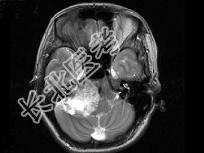

- 单项选择题女,45岁, 右侧听力下降伴行走不稳2个月,根据所提供图像, 最可能的诊断是 ( )

A、右侧脑膜瘤

B、右侧胆脂瘤

C、右侧皮样囊肿

D、右侧神经纤维瘤

E、右侧听神经瘤